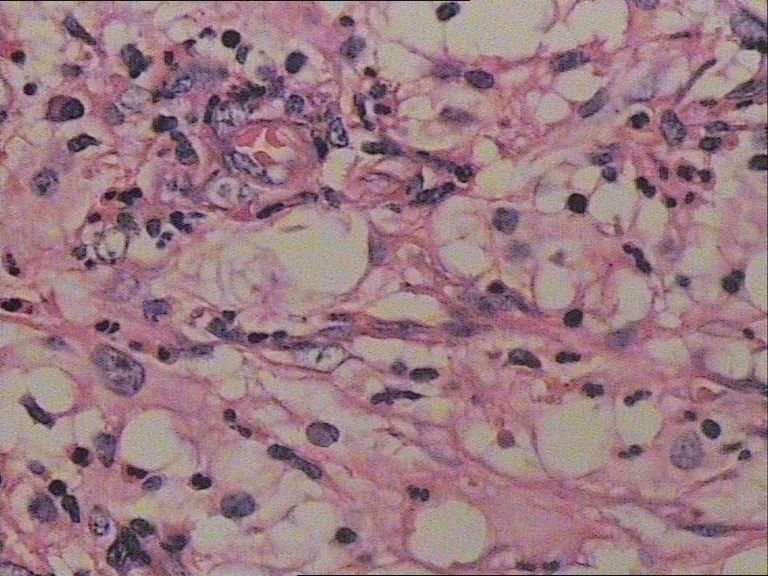

患者 女 47岁 腰部皮下肿块5x4cm,皮肤表面灰褐色,无隆起,无压痛。体格检查无其他异常。

涂片内见较多组织细胞和多核巨细胞。肉芽肿性炎。

是的,单核及多核组织细胞是本病不特异但恒定的特点。

诊断是Rosai-Dorfman病。